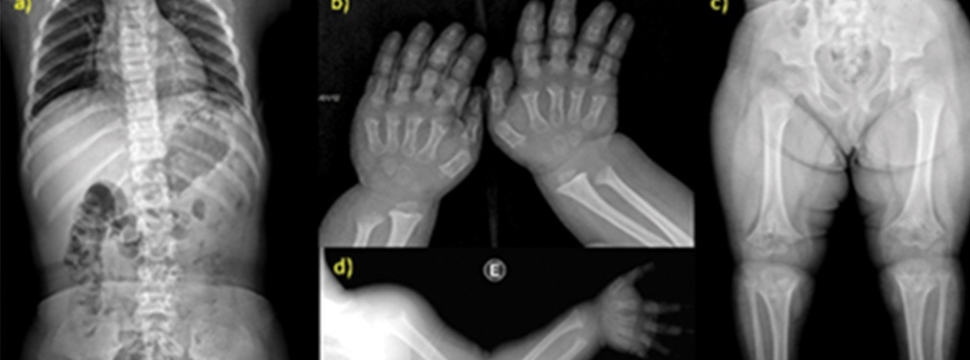

Рахит рентген

Рахит рентген 136 фото